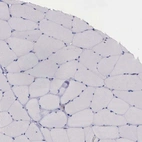

Immunohistochemistry analysis in human placenta and skeletal muscle tissues using HPA000649 antibody. Corresponding NAGA RNA-seq data are presented for the same tissues.